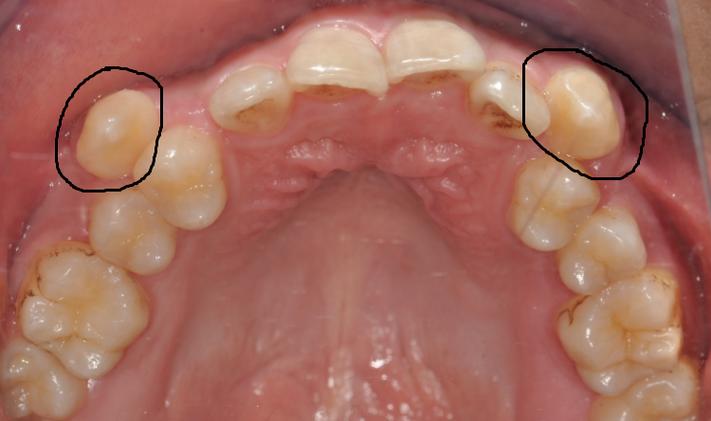

虎牙是口腔中“牙根最长、最坚固”的牙齿之一,位于口角两侧,是牙齿排列中“最后的守门员”,从功能角度看,虎牙具有强大的撕裂食物能力,是咀嚼系统中的重要“切割工具”;从美学角度看,它位于牙弓转折处,支撑着口角和鼻翼的丰满度,对面部轮廓(尤其是“苹果肌”的饱满度)至关重要,虎牙萌出较晚(通常12-13岁),且牙根粗壮、位置靠前,对维持牙弓的稳定性和邻牙排列有不可替代的作用,正畸医生普遍认为,只要虎牙本身健康(无严重龋坏、根尖病变等),且能通过移动纳入牙弓,就应尽力保留,而非轻易拔除。

- 虎牙位置严重异常:如低位、水平阻生虎牙,完全埋伏在颌骨内,且通过外科手术导萌风险过高(如靠近重要神经、血管),或导萌后仍无法建立正常咬合。